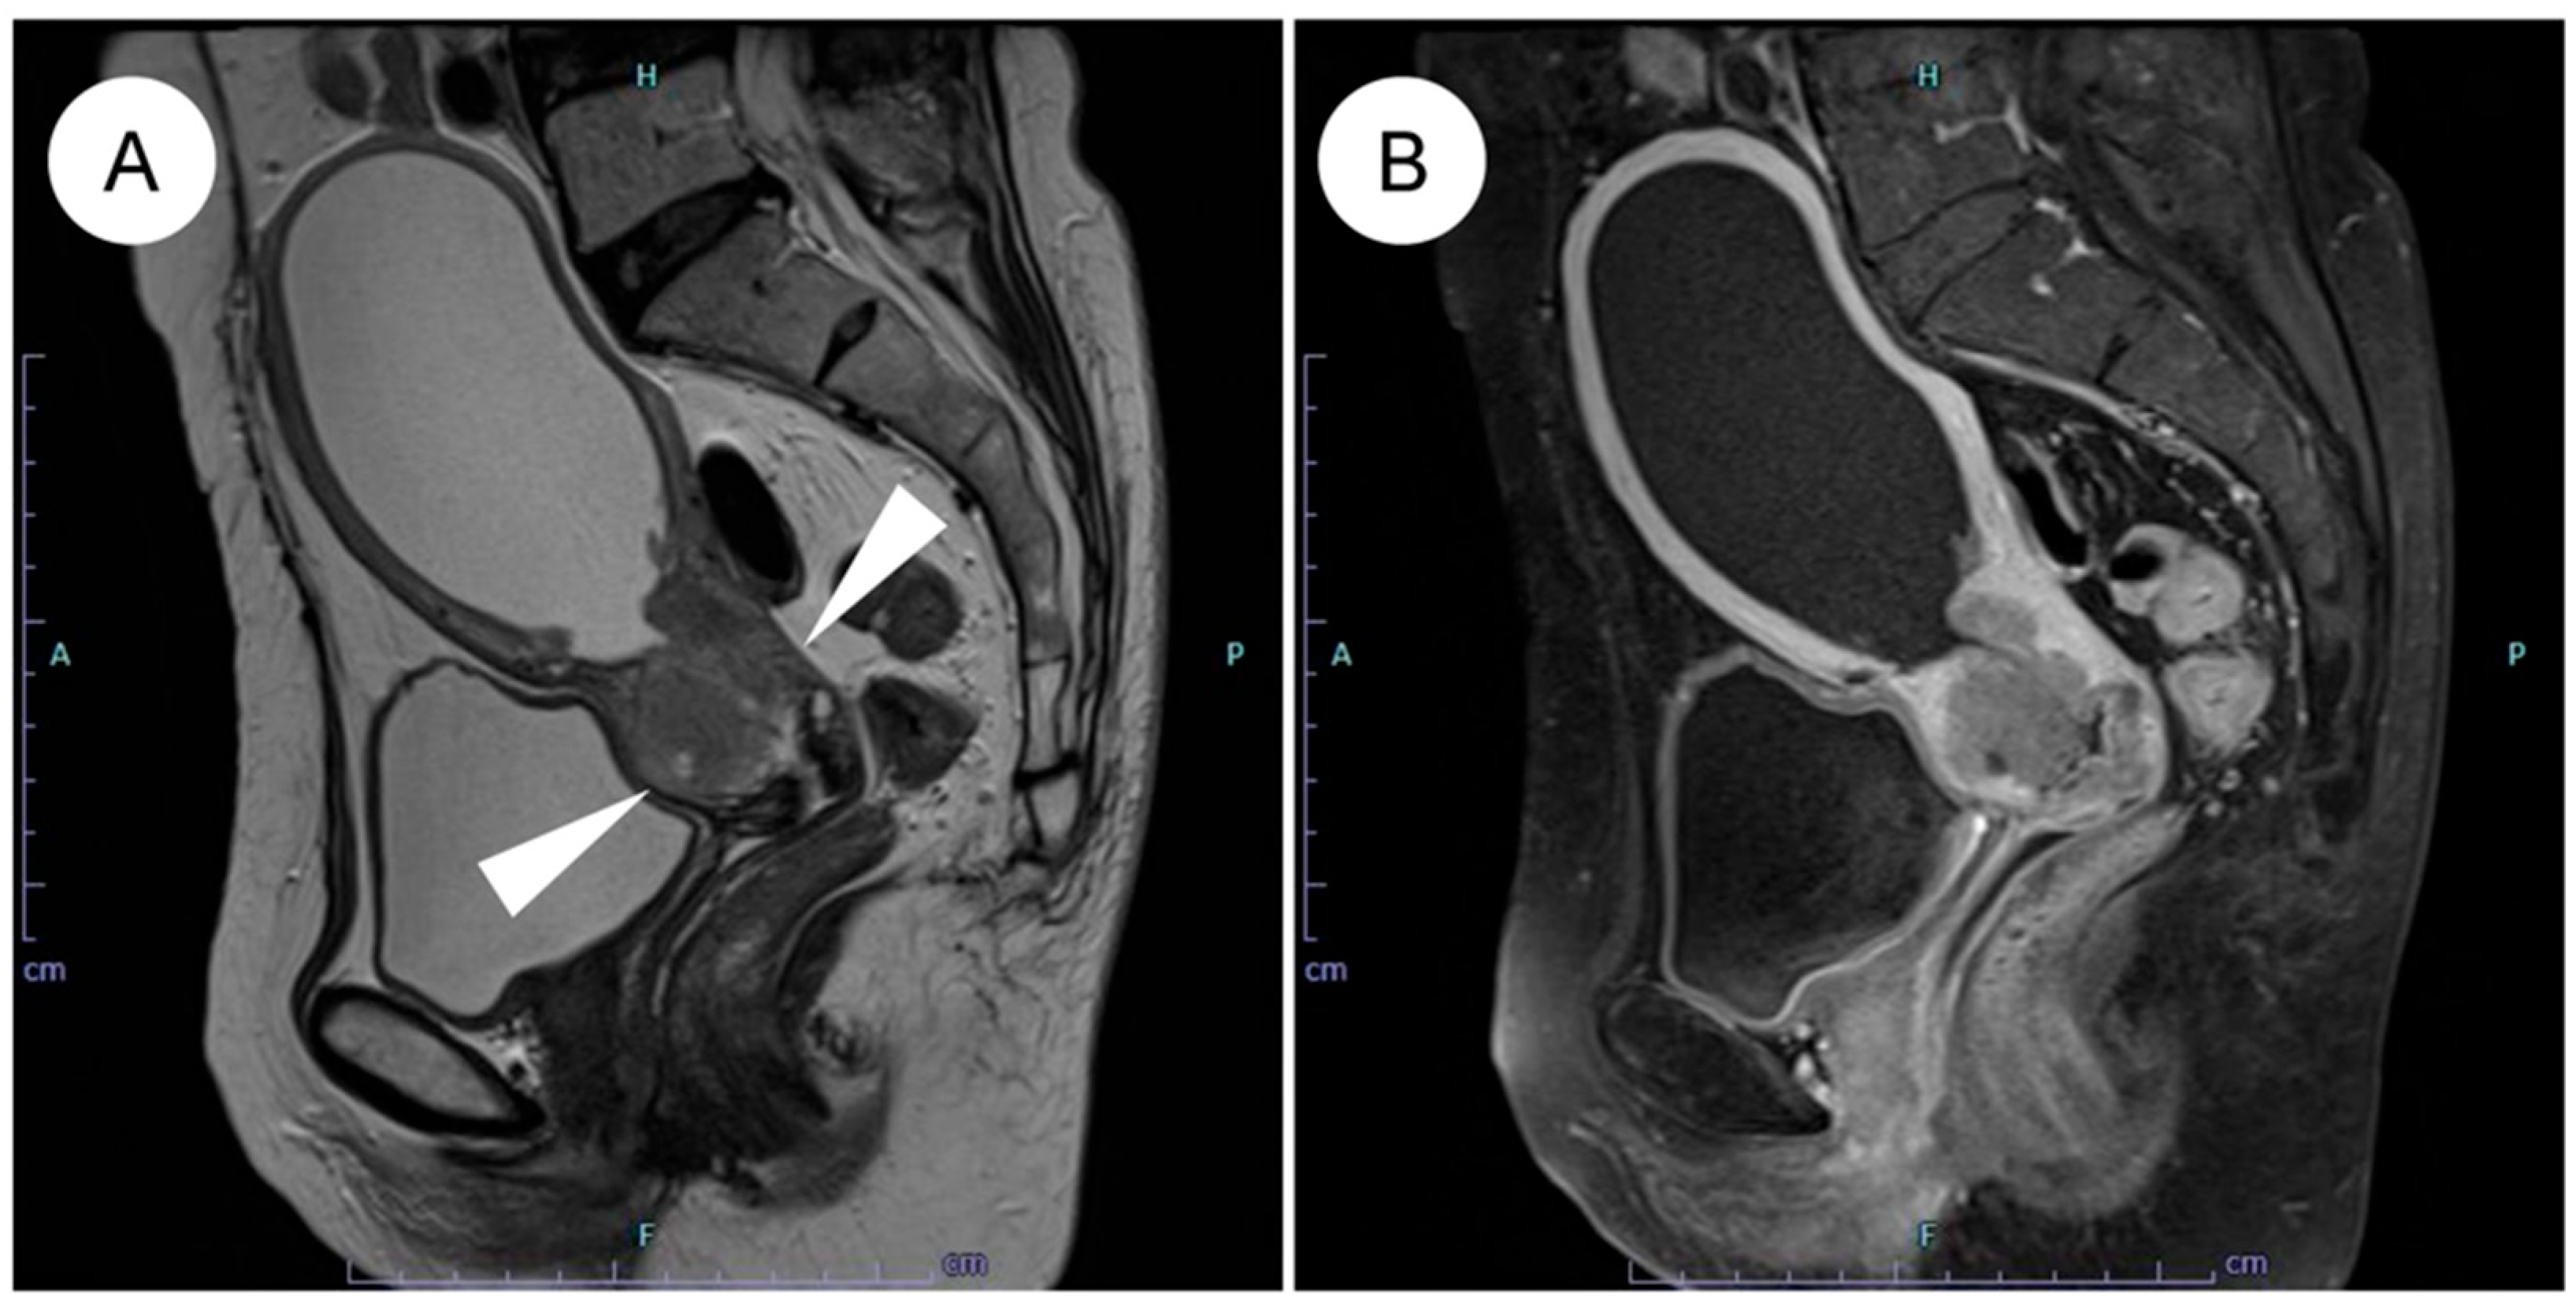

Magnetic resonance imaging (MRI) is regarded as the optimal modality for assessing local invasion in cervical cancer [47], and several characteristic MRI findings have been described for GAS (Figure 1) [42,43,44,45]. (1) Tumor location: the tumor often involves the entire cervix, including the upper portion (13 of 18 cases) [42]. SCC and UEA tend to be localized predominantly to the lower cervix, including the squamocolumnar junction (SCJ), where HPV infection arises [42,43]. By contrast, because LEGH, a potential precursor lesion of GAS, is frequently located in the upper endocervical canal, GAS also tends to extend into the upper cervix [5,42,48]. (2) Growth pattern: a diffuse infiltration pattern is the predominant pattern of growth (17 of 18 cases) [42], whereas SCC and UEA generally show a mass-forming pattern [42]. This inwardly expanding, deeply infiltrative pattern reflects the highly aggressive nature of GAS and may contribute to underestimation of the true extent of disease on imaging [42,43,44,46]. (3) Associated cystic changes: microcysts (≦3 mm) or macrocysts (>3 mm) are frequently observed (14 of 18 cases) [42], reflecting the highly mucinous (mucin-producing) nature of GAS [42]. In some cases, GAS exhibits a “cosmos pattern,” similar to that seen in LEGH, characterized by clusters of microcysts centrally and surrounding macrocysts peripherally; in such situations, differentiation from LEGH based on MRI alone can be challenging [42,49,50]. (4) Solid tumor formation: although GAS was previously recognized mainly as a multilocular cystic mass, it is now appreciated that most cases appear predominantly as solid tumors on MRI [42,43,45,49]. (5) Intrauterine fluid collection: intrauterine fluid collection is frequently observed (13 of 18 cases) [42]. This finding is thought to result from inward tumor growth with diffuse stromal infiltration, which reduces cervical tissue compliance and narrows the endocervical canal, together with copious mucin production [42].

Figure 1.

MRI features of HPV-independent gastric-type endocervical adenocarcinoma. (A) On sagittal T2-weighted imaging, an endophytic, mildly hyperintense mass is seen in the upper cervix (white arrowheads), showing diffuse infiltrative growth with small intratumoral cysts and associated hydrometra. (B) On post-contrast T1-weighted imaging, the tumor demonstrates mild enhancement. Note the mild enhancement compared to the typically more avid enhancement seen in usual-type adenocarcinoma.